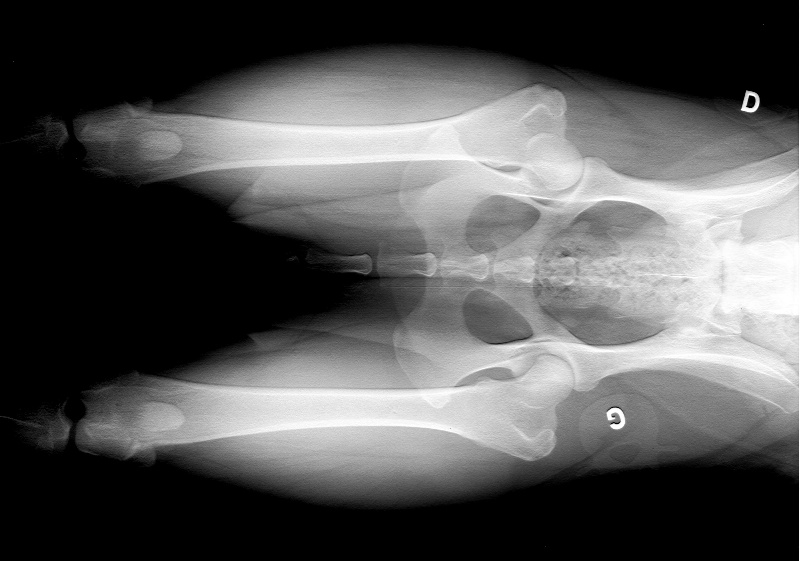

radio dysplasie

compte rendu dysplasie

Test de comportement RACP : apte dysplasie : B |